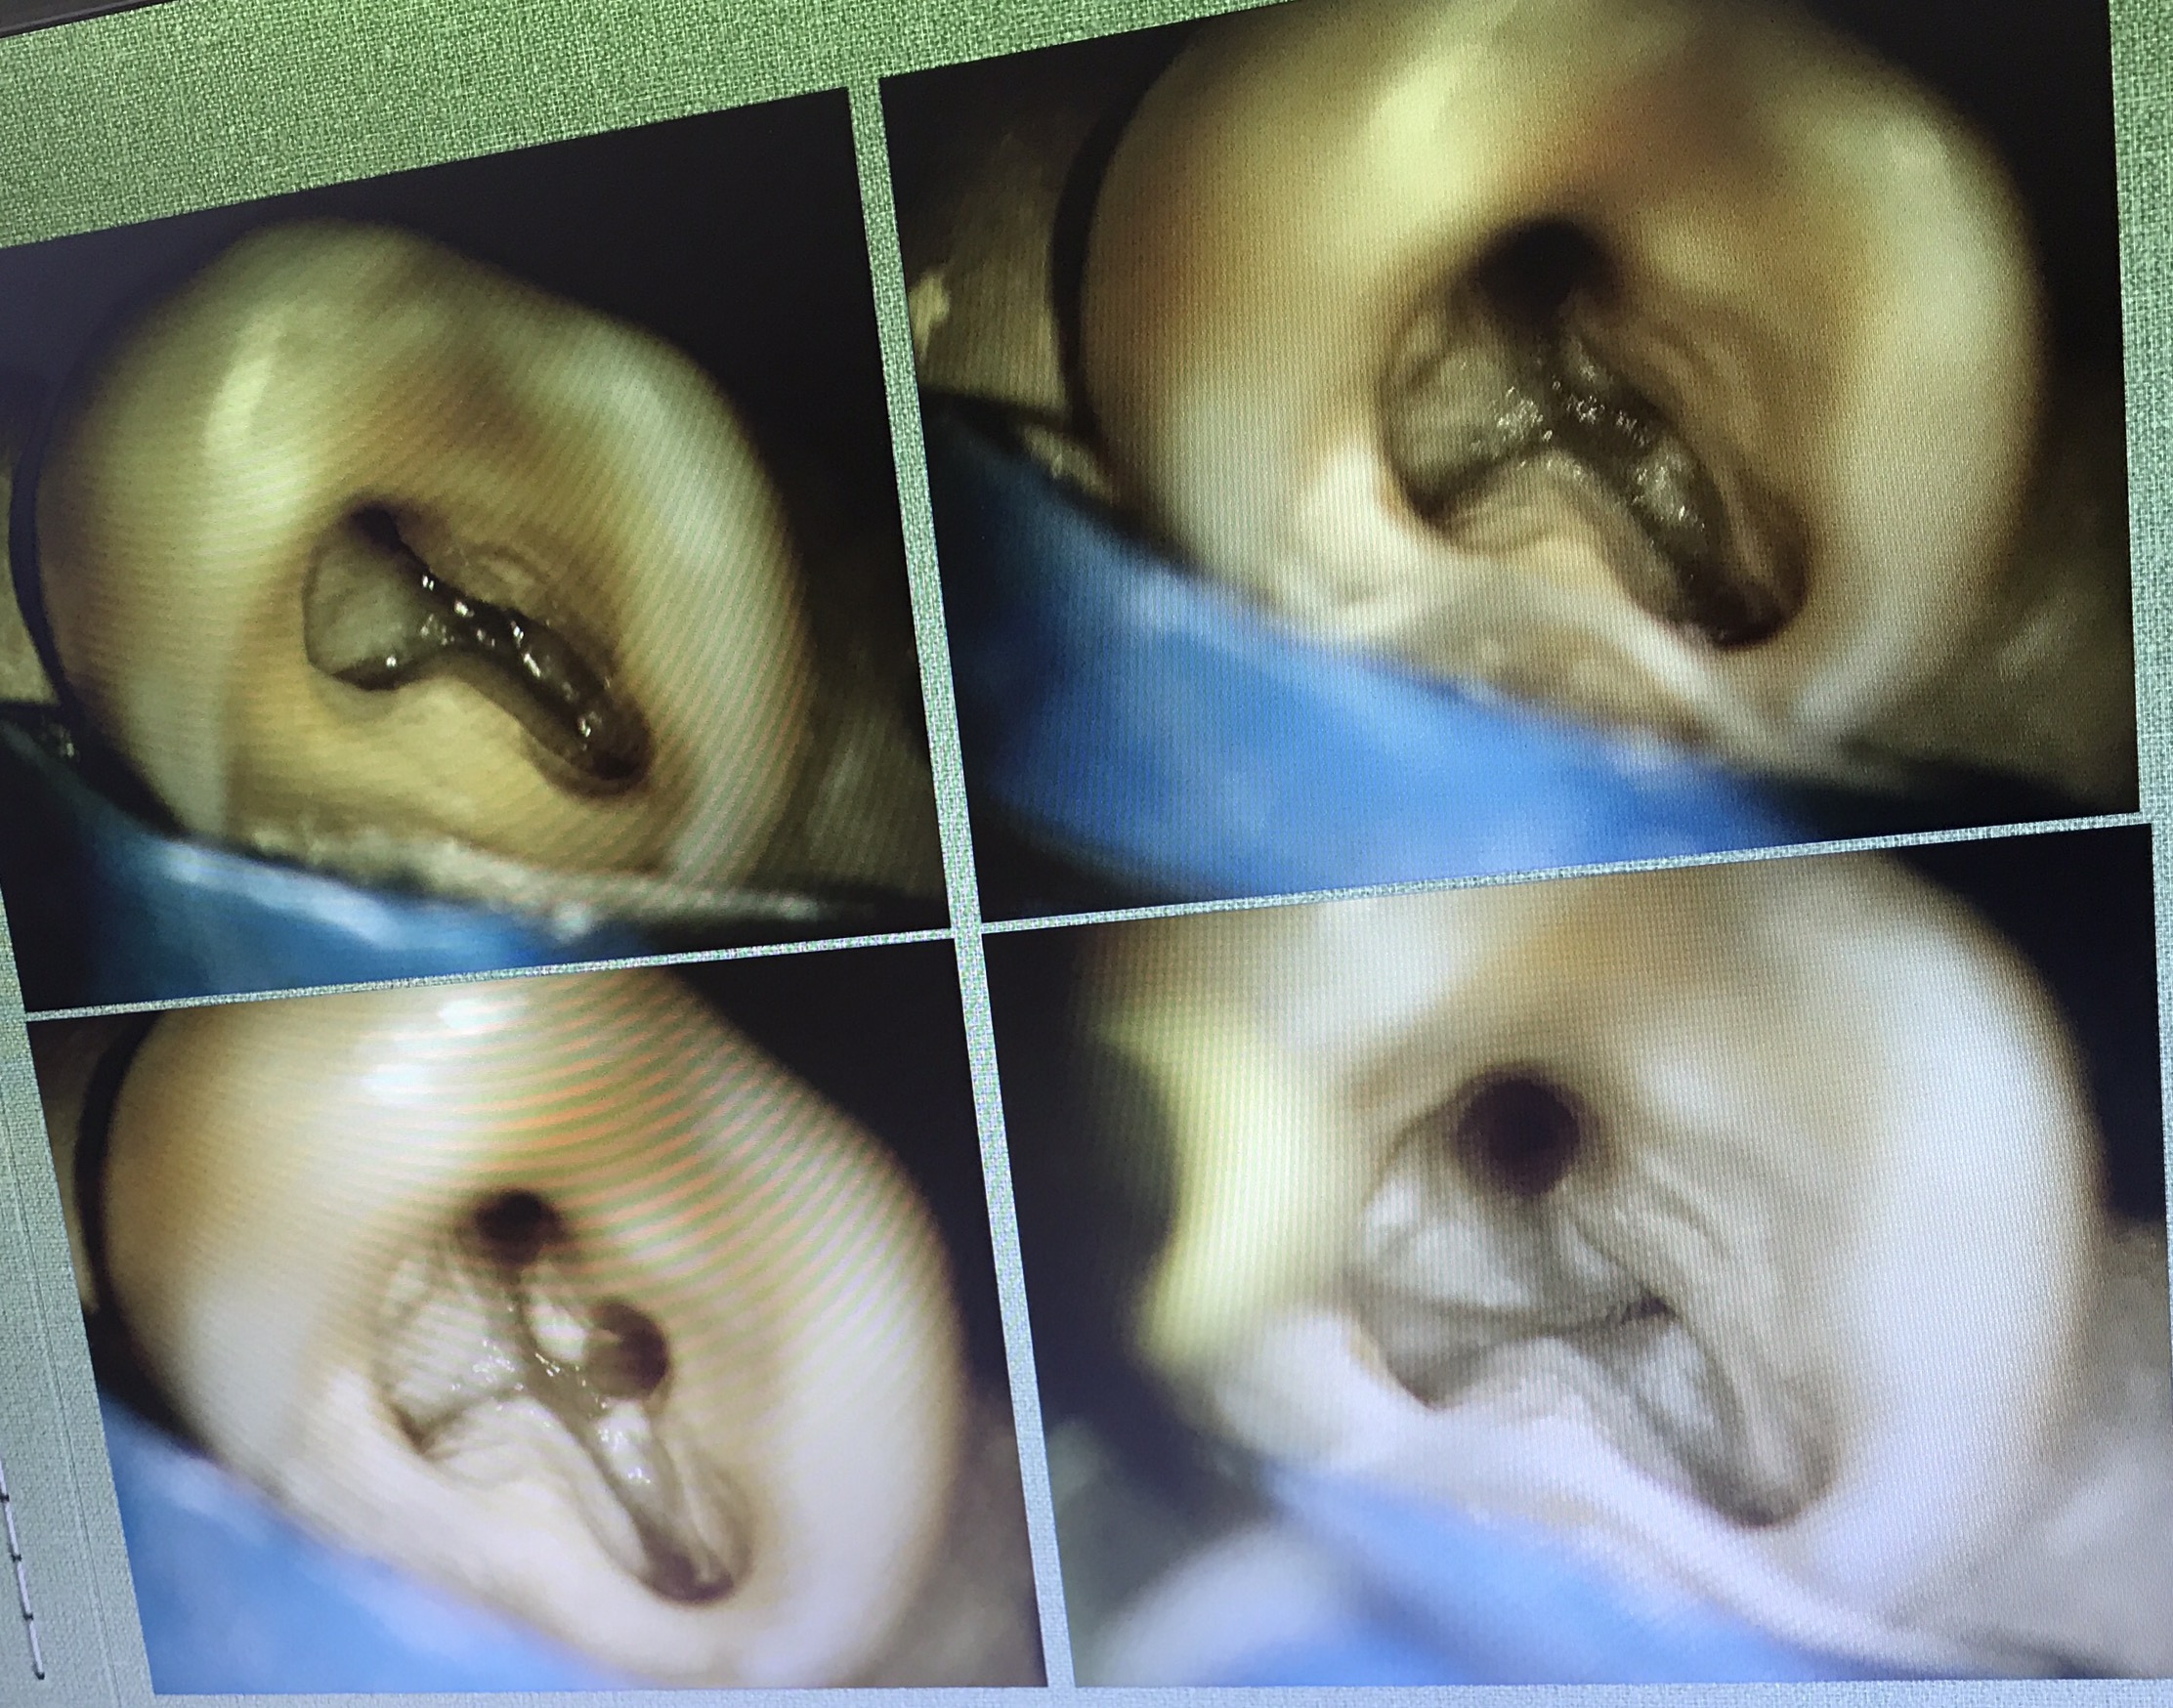

มี VDO demon การใช้งานมาฝากนิดหน่อยครับ แสดงวิธี Locate canal

อันนี้คือ case จริงครับ ส่วนที่ Outline ไว้ตรงกลางคือ รอย Perforate

อีก case

จุดสีเหลือง คือ canal ที่ถูกต้อง

วงกลมสีแดง แสดงส่วนที่ถูก repair ด้วย MTA